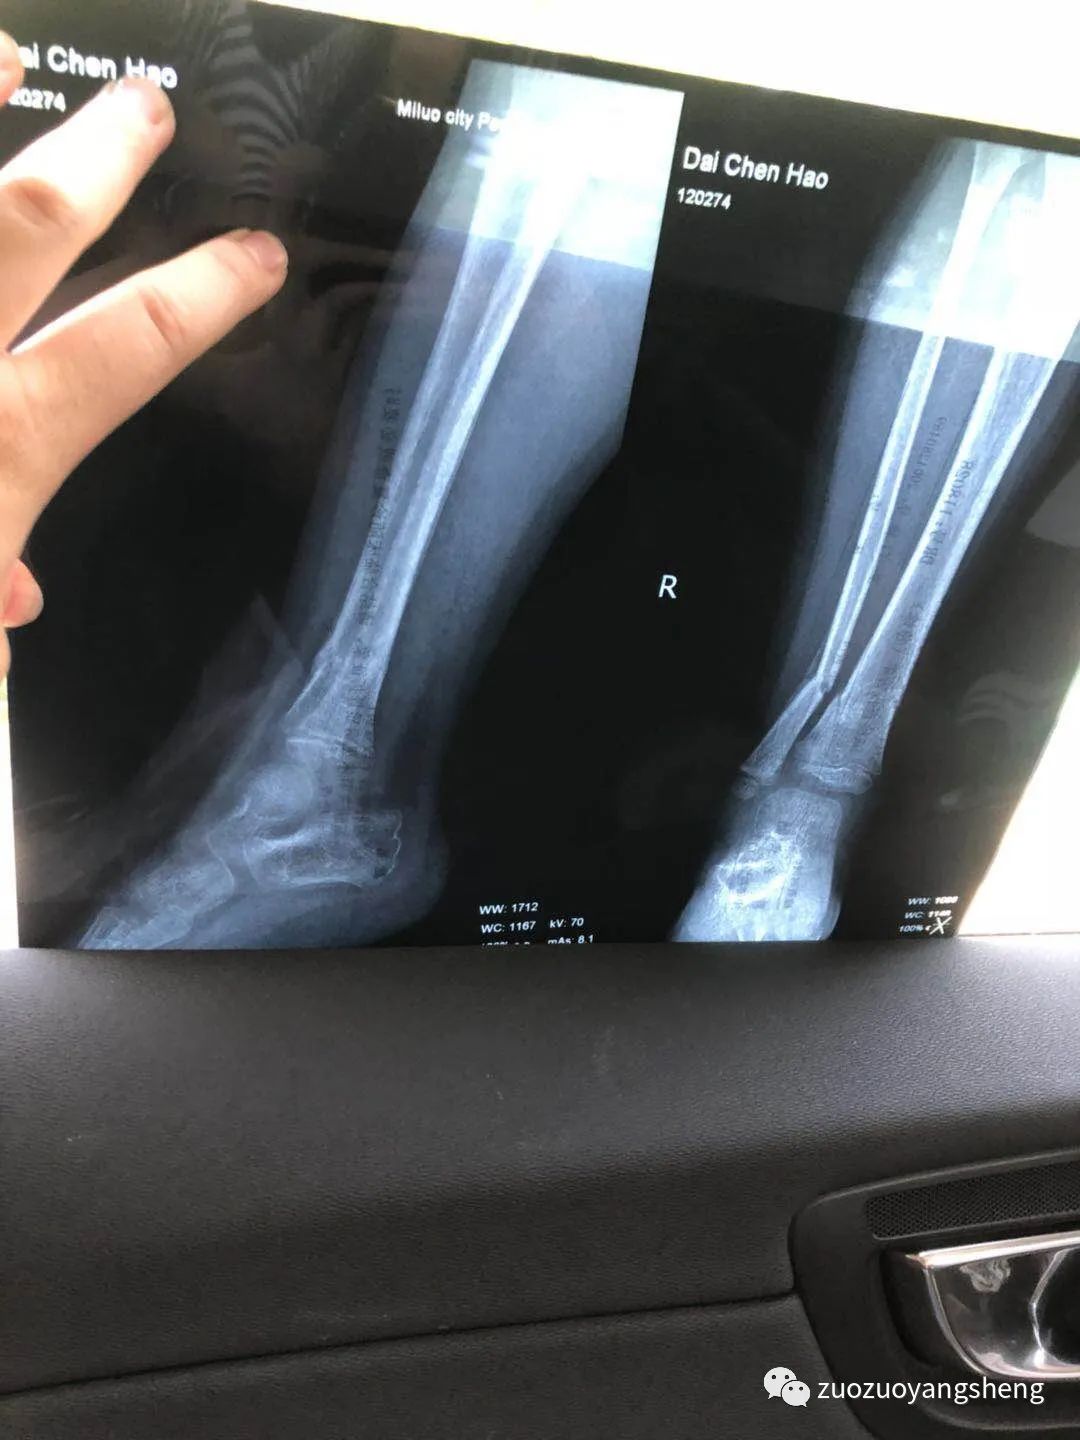

也许是感受到了我的变化,拍片子的时候他真的很乖。只是意外并不因为他的懂事而对他网开一面,结果显示右胫腓骨下端骨折、挨着的胫骨处有细微裂痕。

附检测单据:

孩子因为拆了石膏,安全感全失,吵闹了两天腿疼。同学说这个是正常现象,看了拍照发给他的片子后说,骨裂还是这么多要注意一下就好。